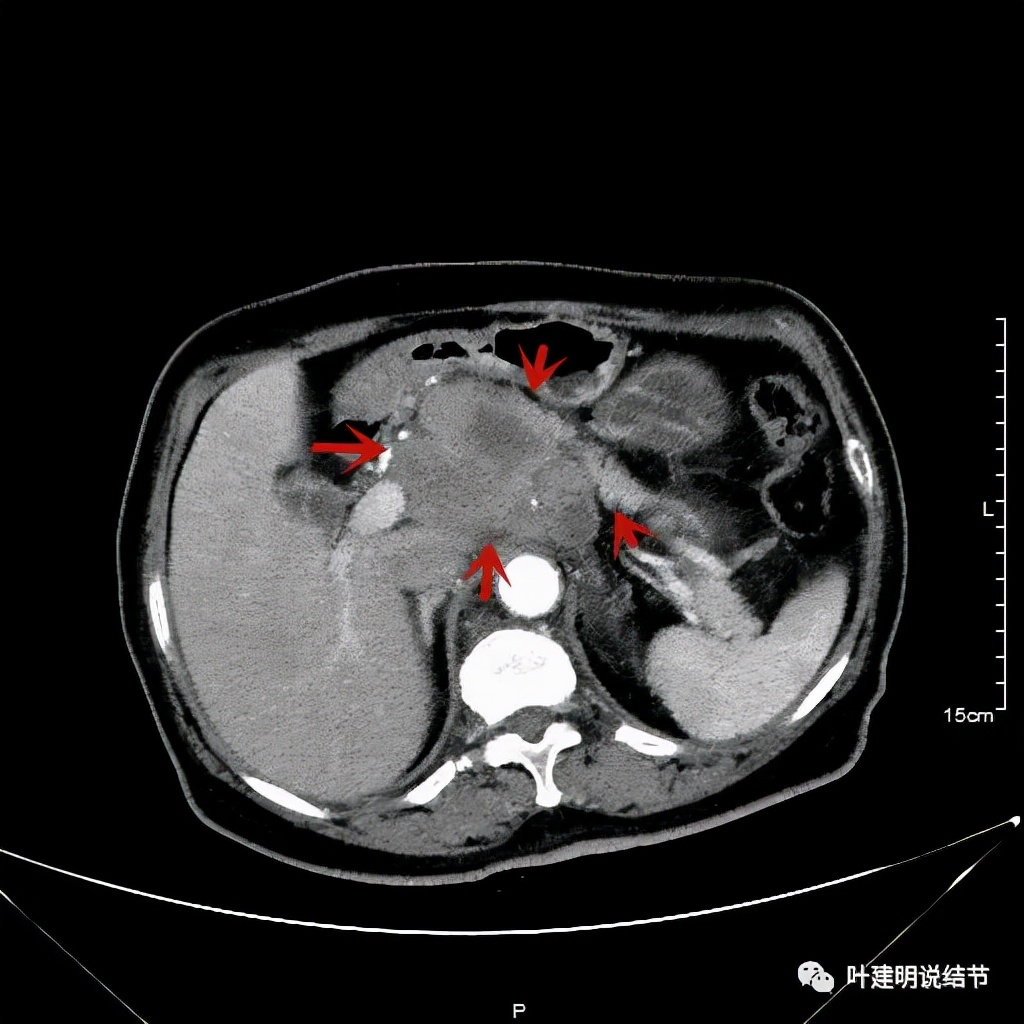

上图左侧是治疗前的,右侧图像是差不多同一层面(因原肿瘤挤压,很难完全找出同一平面),可见病灶明显缩小改善了!下面是复查时的CT影像报告:

之后又再经过一个周期后的对比:

上图同样左侧是治疗前的,右侧经过2周期免疫加化疗后复查的,可见病灶缩小甚至超过9成。下面是治疗前与后来于6月底复查的:

可见经过4个多月的治疗,转移灶已经几乎看不出来了!目前患者无任何不适,正常进食,也无腹部症状或体征,仍在持续特瑞普利单抗维持治疗中。我们期待其更长久的获益与持久的疗效,为其他晚期食管癌积累自己的实战经验(开会或文献上别人的介绍没有自己遇到的如此直观,也没有如此深的印象。所以我一直觉得临床经验,尤其自己亲身经历积累的经验才更有说服力,也更有感受)。